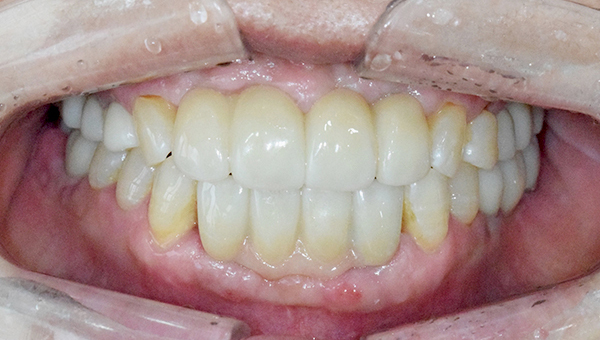

치료사례임플란트

강*란 임플란트 시술 사례

전체 임플란트

2025.02.07

치료 전

2025.08.19

치료 후